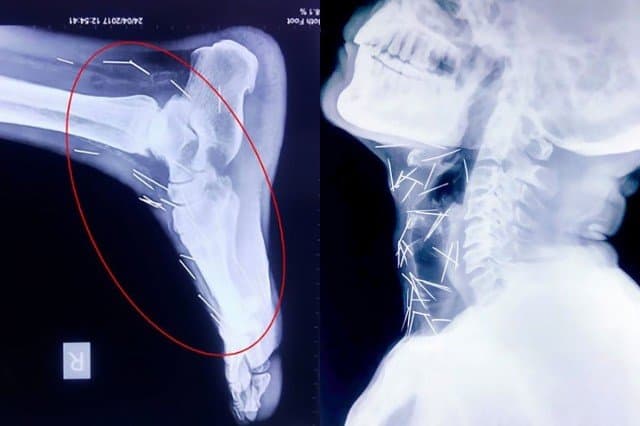

ผงะ ภาพฟิล์มเอ็กซเรย์ชายอินเดียมี 'หมุด-เข็ม' ฝังทั่วร่าง 75 ชิ้น เจ้าตัวงงไม่รู้มาได้ไง